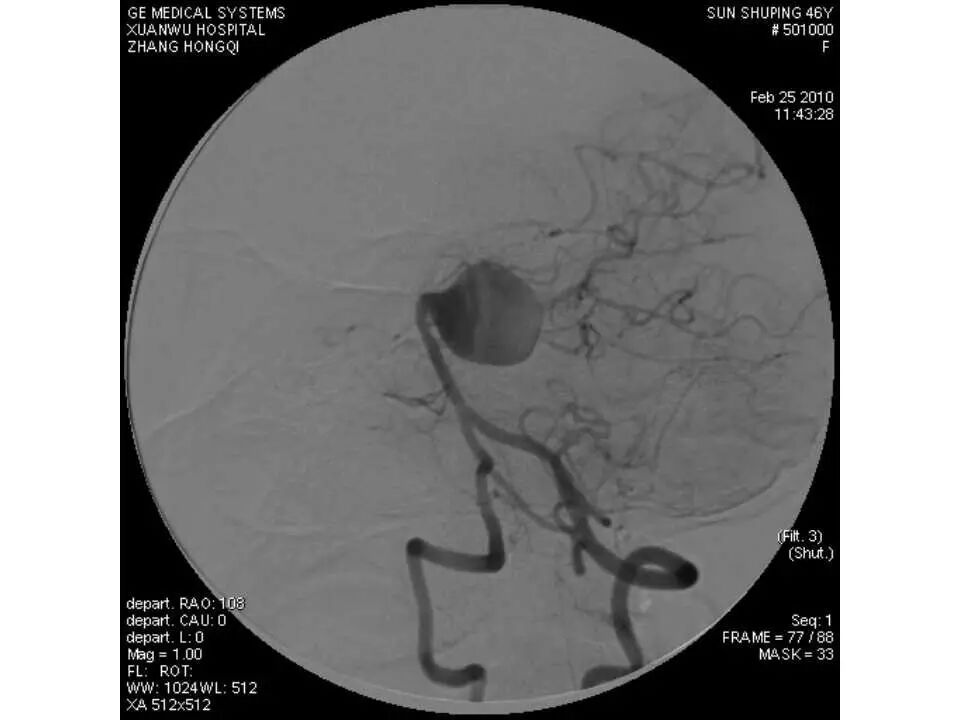

今天为大家分享的是“强生医疗CNV-神经介入专栏”第十五期,由首都医科大学宣武医院何川教授带来的“颅内动脉瘤介入治疗”精彩讲课视频及PPT,欢迎观看、阅读。文章仅代表作者个人观点,如有不同见解,欢迎同道斧正!

何川 ,首都医科大学宣武医院副主任医师,中国医师协会神经介入专业委员会常务委员,长期从事脑血管病和脊髓血管病的手术及介入治疗和相关研究工作。首都医科大学神经外科博士,师从于中国神经介入开创人凌锋教授;日本东北大学医院脑血管病治疗科博士后,师从于日本国脑血管病血管内治疗的开创者高桥教授。